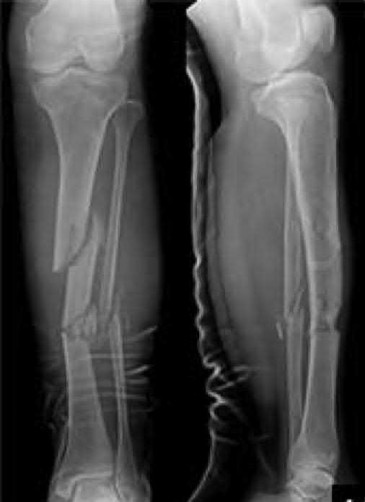

A 55-year-old female presents to the emergency room after falling off her balcony. She sustained the isolated, closed injury shown in Figures A and B. She is otherwise healthy, but routinely smokes 30 cigarettes per day. What would be the most appropriate sequence of treatment steps for definitive management of this injury?

Figures A and B show radiographs of a comminuted AO/OTA C3 fracture of the distal tibia. The most appropriate steps in the management of this patients injury would include: Closed reduction and splinting, external fixation, CT scan, and delayed open reduction internal fixation in this sequence.

Infection and wound healing problems are common with comminuted distal tibia fractures due to an increased incidence of soft-tissue complications associated with the operative management. Patients with a history of diabetes and smoking are at further risk. To decrease the risk of complications in this patient, a two-staged, delayed open reduction internal fixation technique is the best option for the treatment of severe pilon fractures.

Patterson et al. reviewed 23 consecutive patients with comminuted distal tibia fractures. They showed 0% infections or wound-healing problems in their patient population treated with a two-staged protocol. Their protocol involved fibula fixation with an intramedullary implant and application of a medial external fixator to to regain length and restore anatomic alignment. Re-evaluation of the limb occurred ten to fourteen days later for definitive fixation.

Sirkin et al. retrospectively reviewed 40 closed and 82 open pilon fractures (AO types 43A-C) that were treated with staged surgical management (avg. time from ext. fix. to formal reconstruction was 14 days (range 4 to 31) They reported 17% post-operative wound complication in the closed group and 11% post-operative wound complication in the open group (Gustilo Type I-III). They suggest the technique was successful in both closed and open pilon fractures.